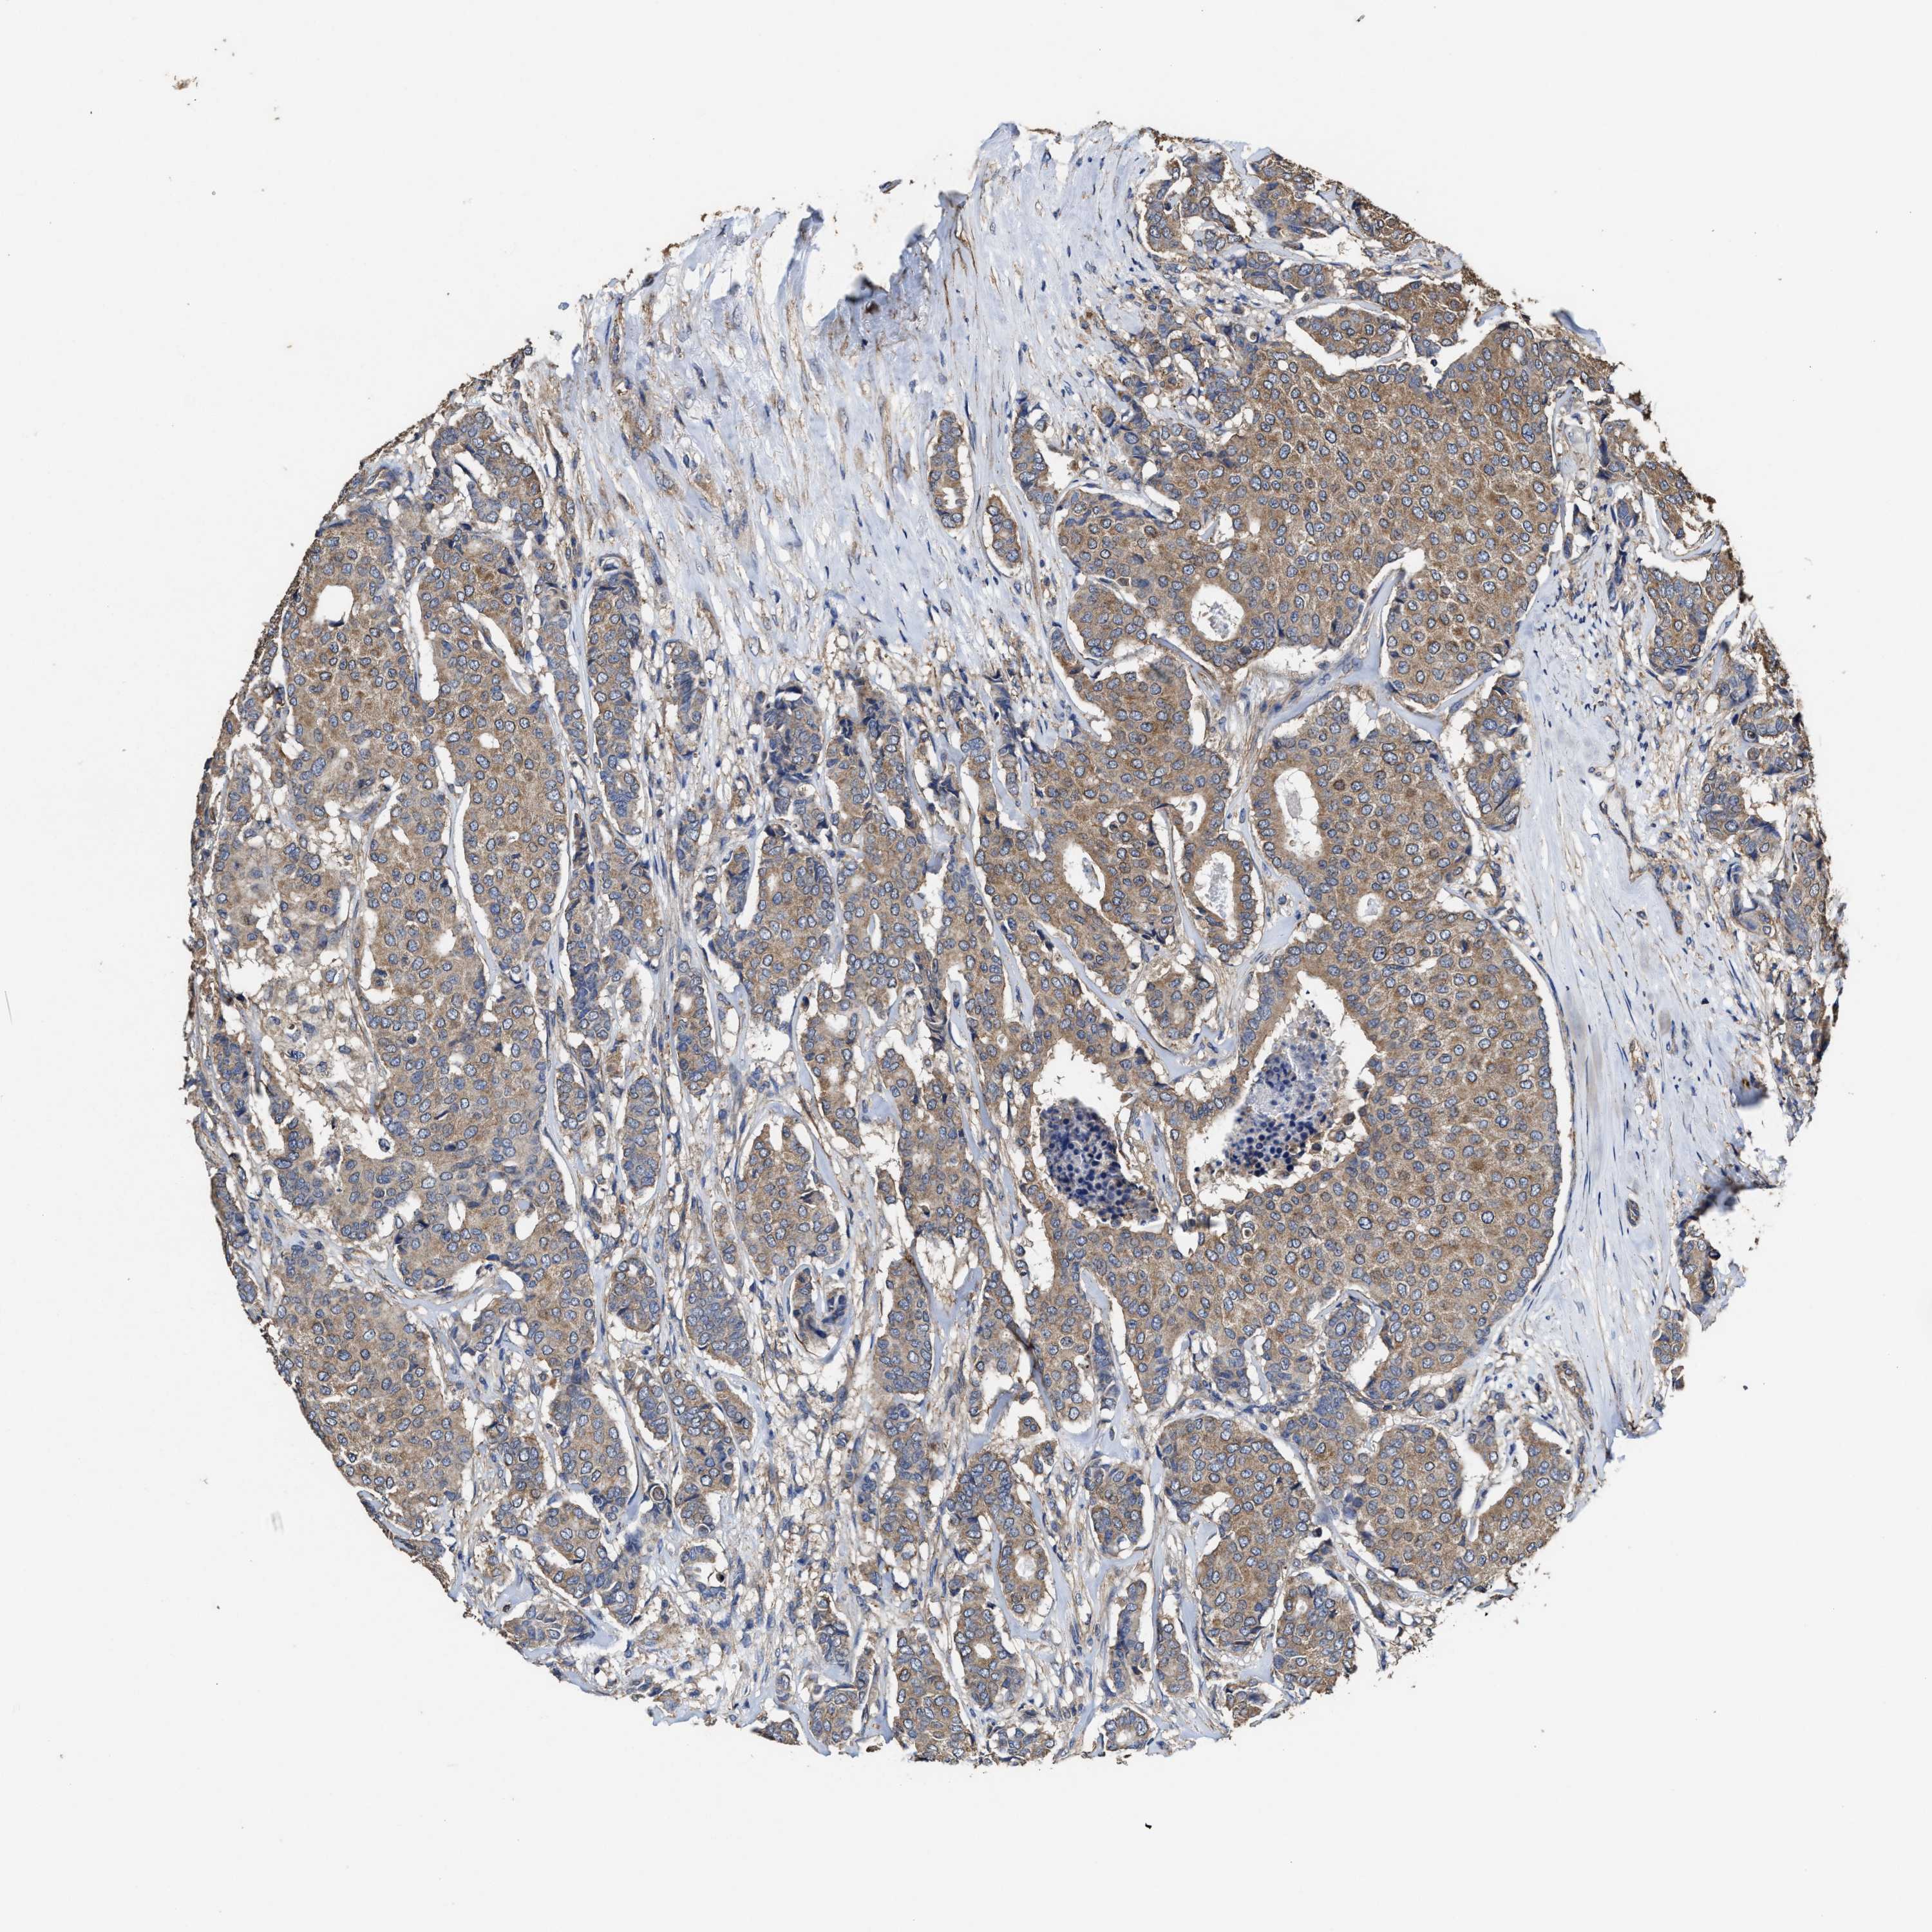

CANCER BREAST CANCER Show tissue menu

BRCA TCGA BRCA VALIDATION PROTEIN EXPRESSION

Breast cancer

Human cancer

Breast invasive carcinoma

SFXN4 is not prognostic in Breast Invasive Carcinoma (TCGA)